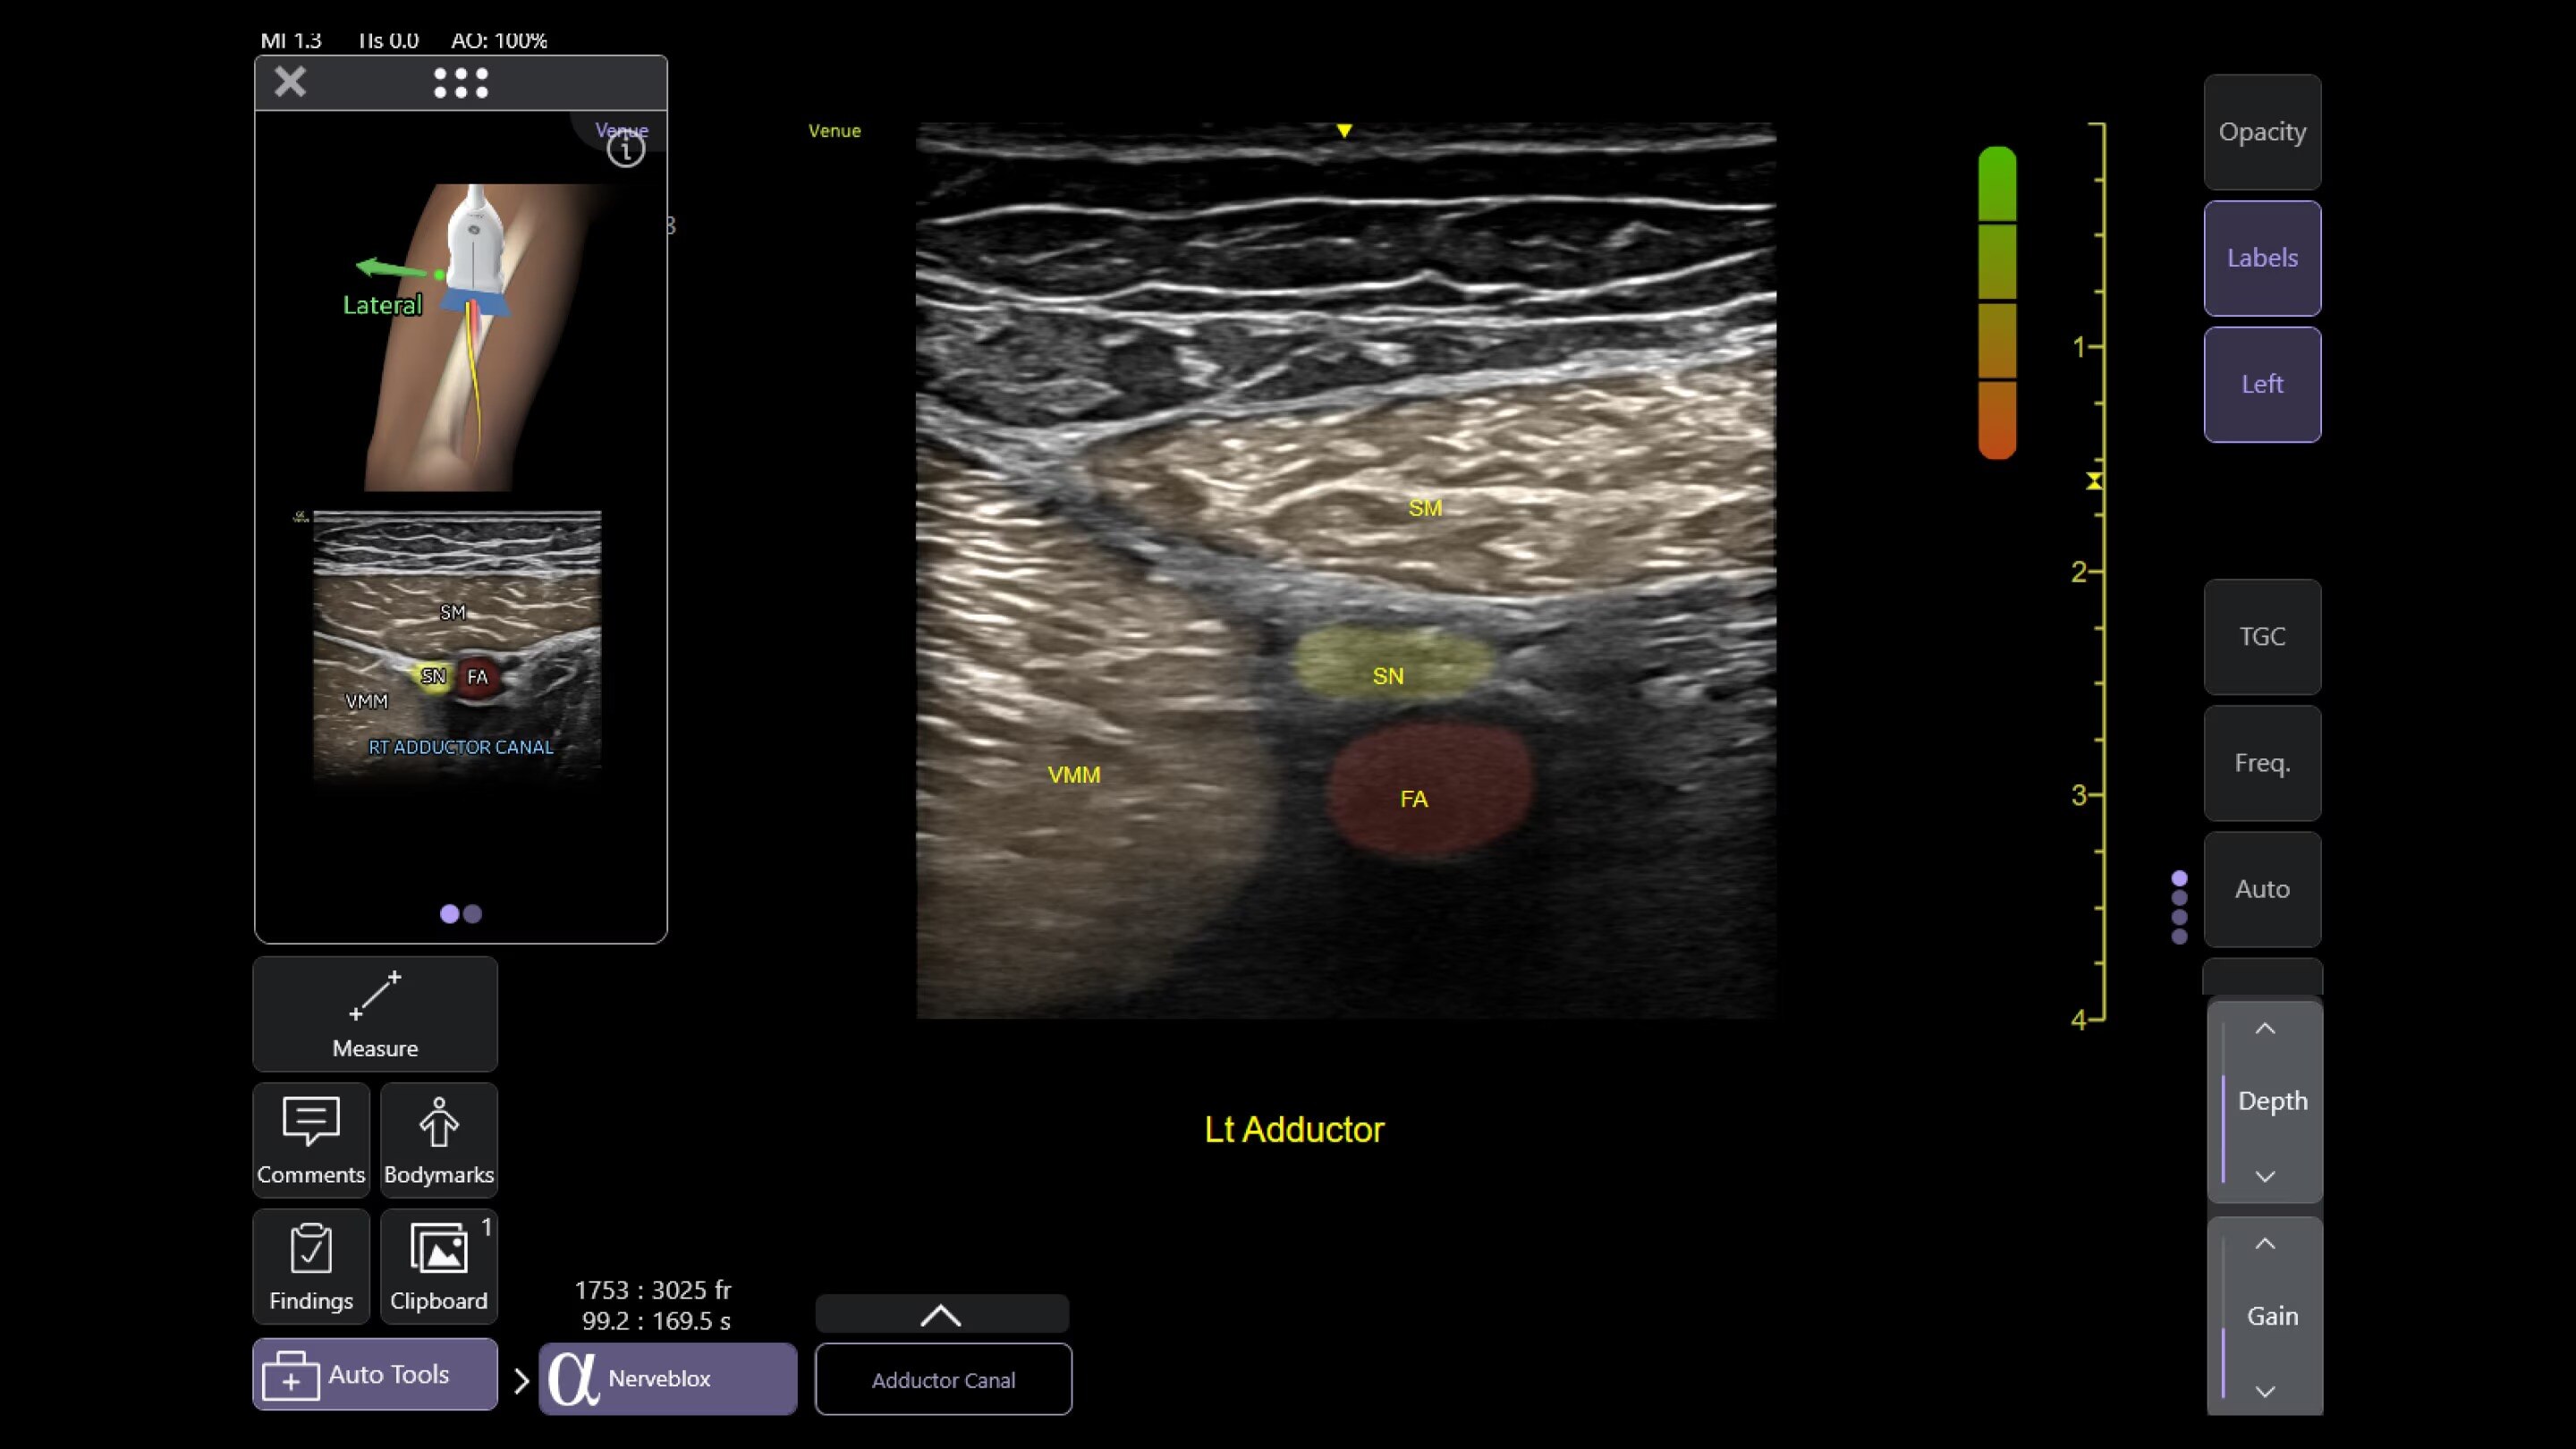

Catheter to Vessel Ratio

Accurate catheter selection tool

Selecting the wrong sized catheter can lead to catheter related thrombosis.2 Catheter to Vessel Ratio is a measurement tool that supports clinicians in selecting the appropriate sized catheter based on vessel diameter.